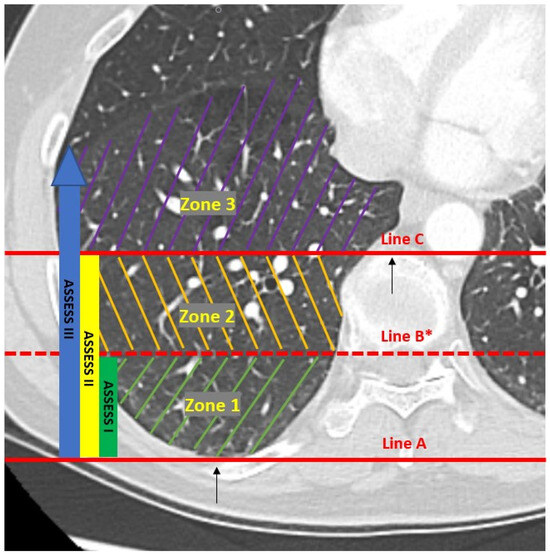

Severity of Atelectasis during Bronchoscopy: Descriptions of a New Grading System (Atelectasis Severity Scoring System—“ASSESS”) and At-Risk-Lung Zones

Khan, A.; Bashour, S.; Sabath, B.; Lin, J.; Sarkiss, M.; Song, J.; Sagar, A.-E.S.; Shah, A.; Casal, R.F. Severity of Atelectasis during Bronchoscopy: Descriptions of a New Grading System (Atelectasis Severity Scoring System—“ASSESS”) and At-Risk-Lung Zones. Diagnostics 2024, 14, 197. https://doi.org/10.3390/diagnostics14020197